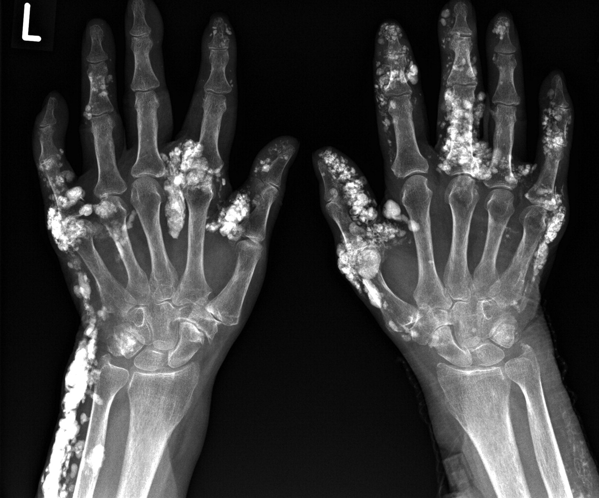

Subcutaneous calcifications

Most common over the fingertips and bony eminences

Renal: Hypertension Chronic kidney disease **Scleroderma renal crisis:** Life-threatening acute renal failure Malignant **hypertension** Musculoskeletal: **Polyarthralgias/arthritis** Flexion contractures Fingers, wrists, and elbows Tendon friction rubs Tendinitis